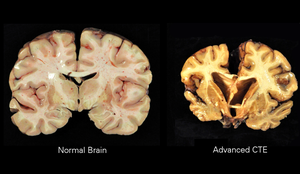

Gross images showing a brain with chronic traumatic encephalopathy (CTE) and a normal brain. (WC/BU)

Chronic traumatic encephalopathy, abbreviated CTE, is a neurodegenerative disease due to repeated trauma.